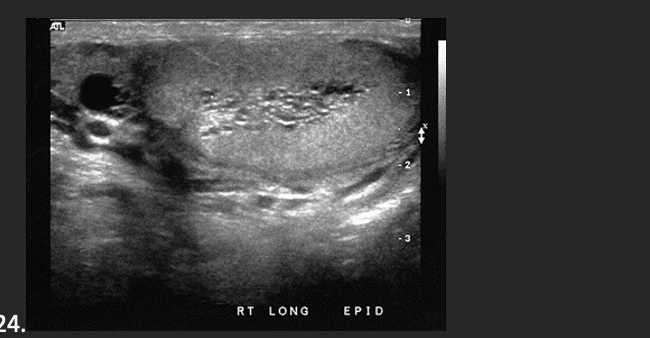

A patient presents with a history of scrotal swelling and tenderness. He denies any scortal trauma on the basis of this clinical history the sonographic findings are most consistent with a

The echogenic structure superior to the testis most likely represents

A. Hydrocele

D. Epidymal Head